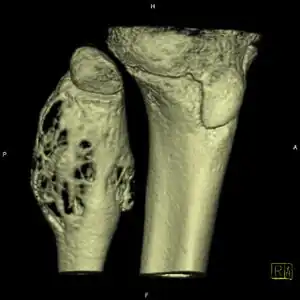

X-ray and CT scan show lytic expansion lesions with clear borders.[1] Expansion of cortex gives the lesion a balloon-like appearance. Larger lesions may appear septated.[10] MRI reveals fluid levels.[1] Bone scan shows outer radiotracer uptake, with a central dark area.[1]

CT scan: ABC fibula